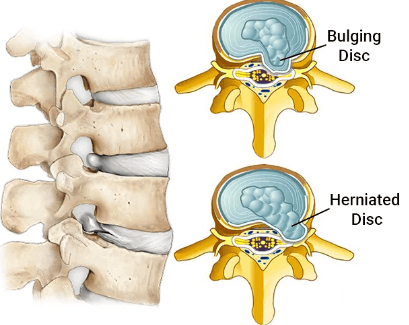

如有脊椎錯位或椎間盤突出, 就有機會壓迫神經線, 令一些症狀出現!